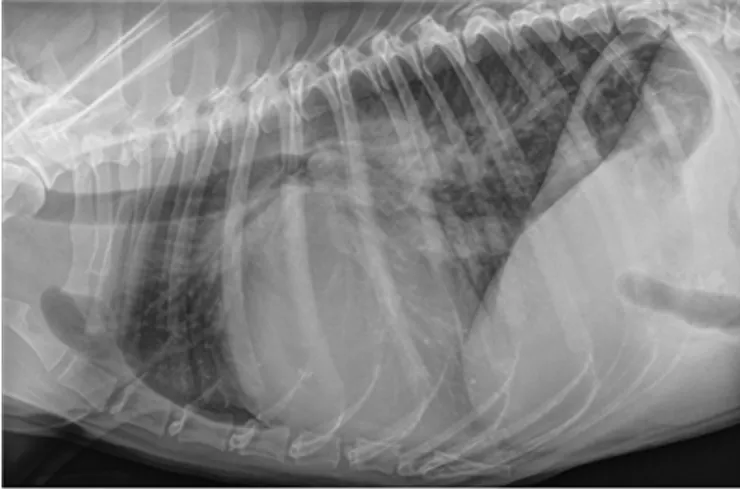

➡️在明顯的病例上, 的確當我們看到擴張的左心房與肺積水加上明顯的心雜音, 就可以診斷是心臟病造成的肺積水。但是總是有遇到一些比較難以區分的時候, 造成的原因有可能是當我們拍xray 時剛好拍到狗狗吐氣時, 肺就會看起來比較實質 (比較“白“)但並不是真的有肺積水。或是遇到年紀大且體型又比較胖的動物,肺部影像當然也會看起來比年輕又瘦的狗“白“。另外像是如果動物同時又有肺臟疾病時肺部影像也會比較難區分。所以如果我們沒有看到明顯左心房變大且肺積水出現在心因性肺積水常出現的位置, 就需要更多的檢查去輔助判斷。

心臟擴張 肺積水

心臟擴張肺積水